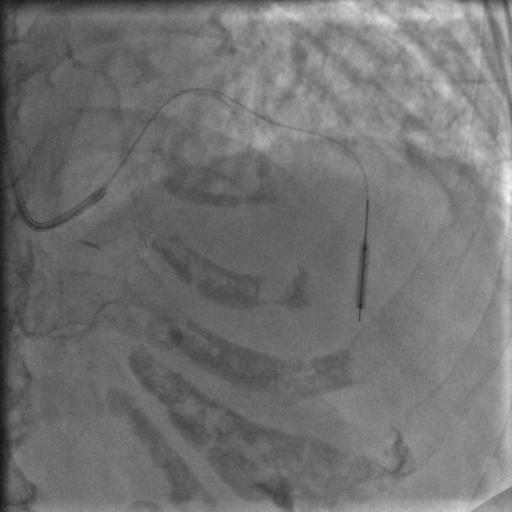

常规消毒、铺巾,再穿刺、放鞘管、送入造影导管、造影,一切顺利,造影结果如下:

图2

图3

图4

比我们想象中的要好,前降支中段闭塞,第一、第二对角支都还在,回旋支、右冠都还好,可以稍微松一口气。